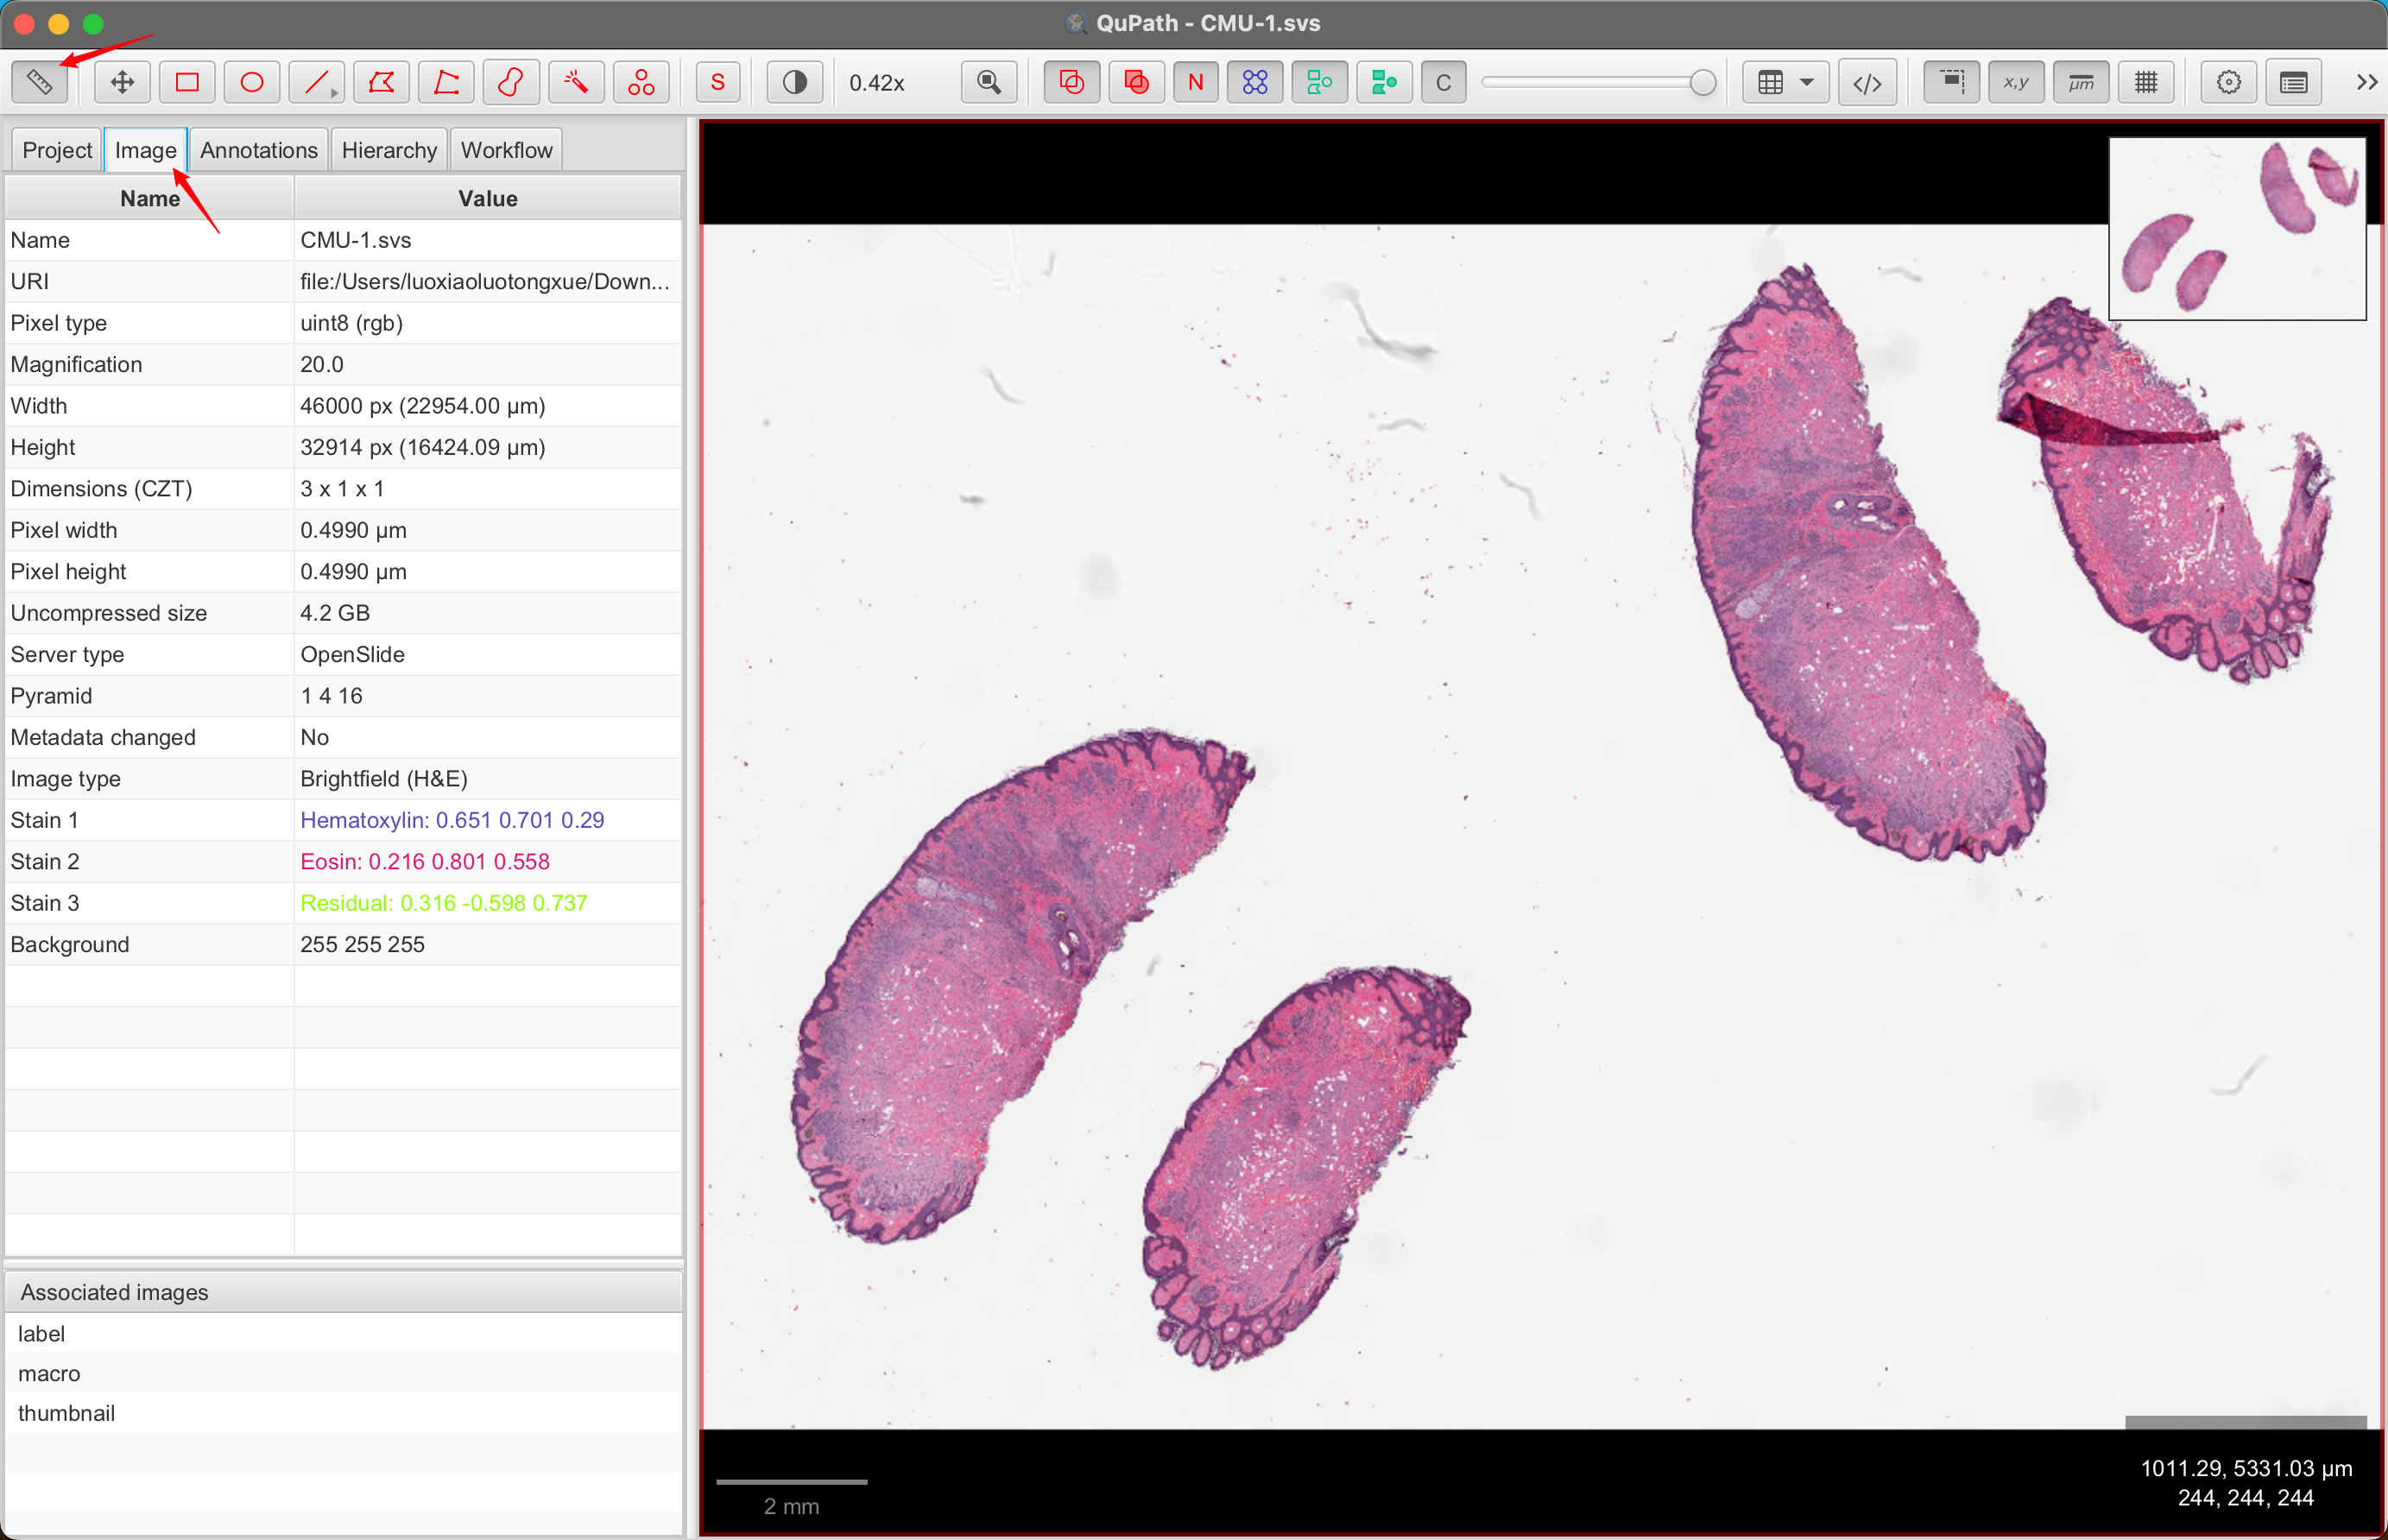

1-3:查看图像属性

通常,QuPath 窗口左侧有一个面板:分析面板。如果没有,请单击工具栏上的分析面板按钮将其打开。

这里有几个选项卡,您稍后会遇到。现在,单击**“图像”**选项卡以获取与您的图像相关的属性表。

1-4:设置像素大小

如果存储在图像文件中,QuPath 应自动获取像素大小并将其显示在**“图像”**选项卡(“像素宽度”和“像素高度”)下。

如果没有,您可以通过双击任一行并输入正确的值来手动设置像素大小。